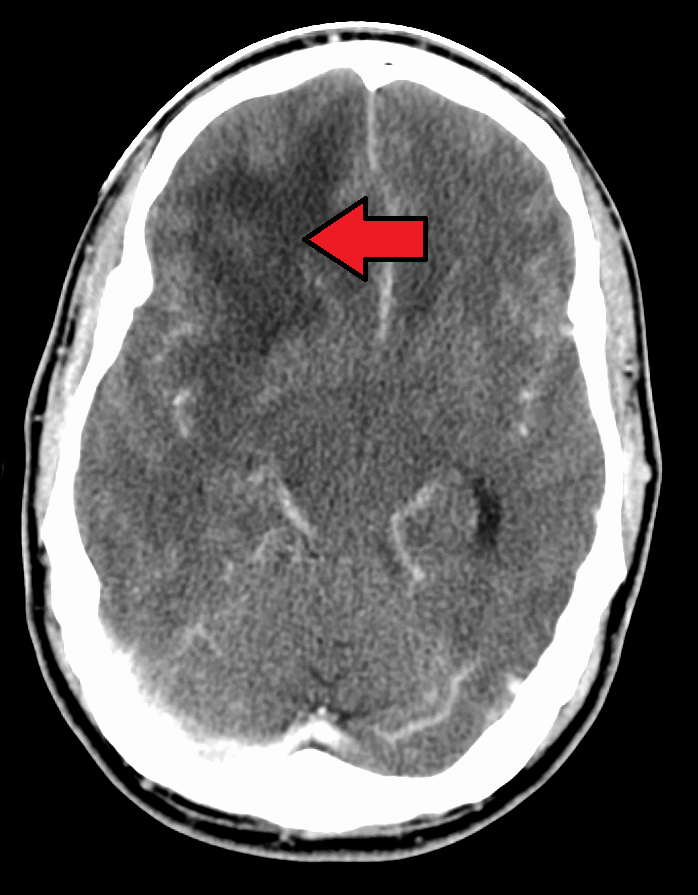

- medical imaging

- Medical imaging (Basic science review) ↩︎